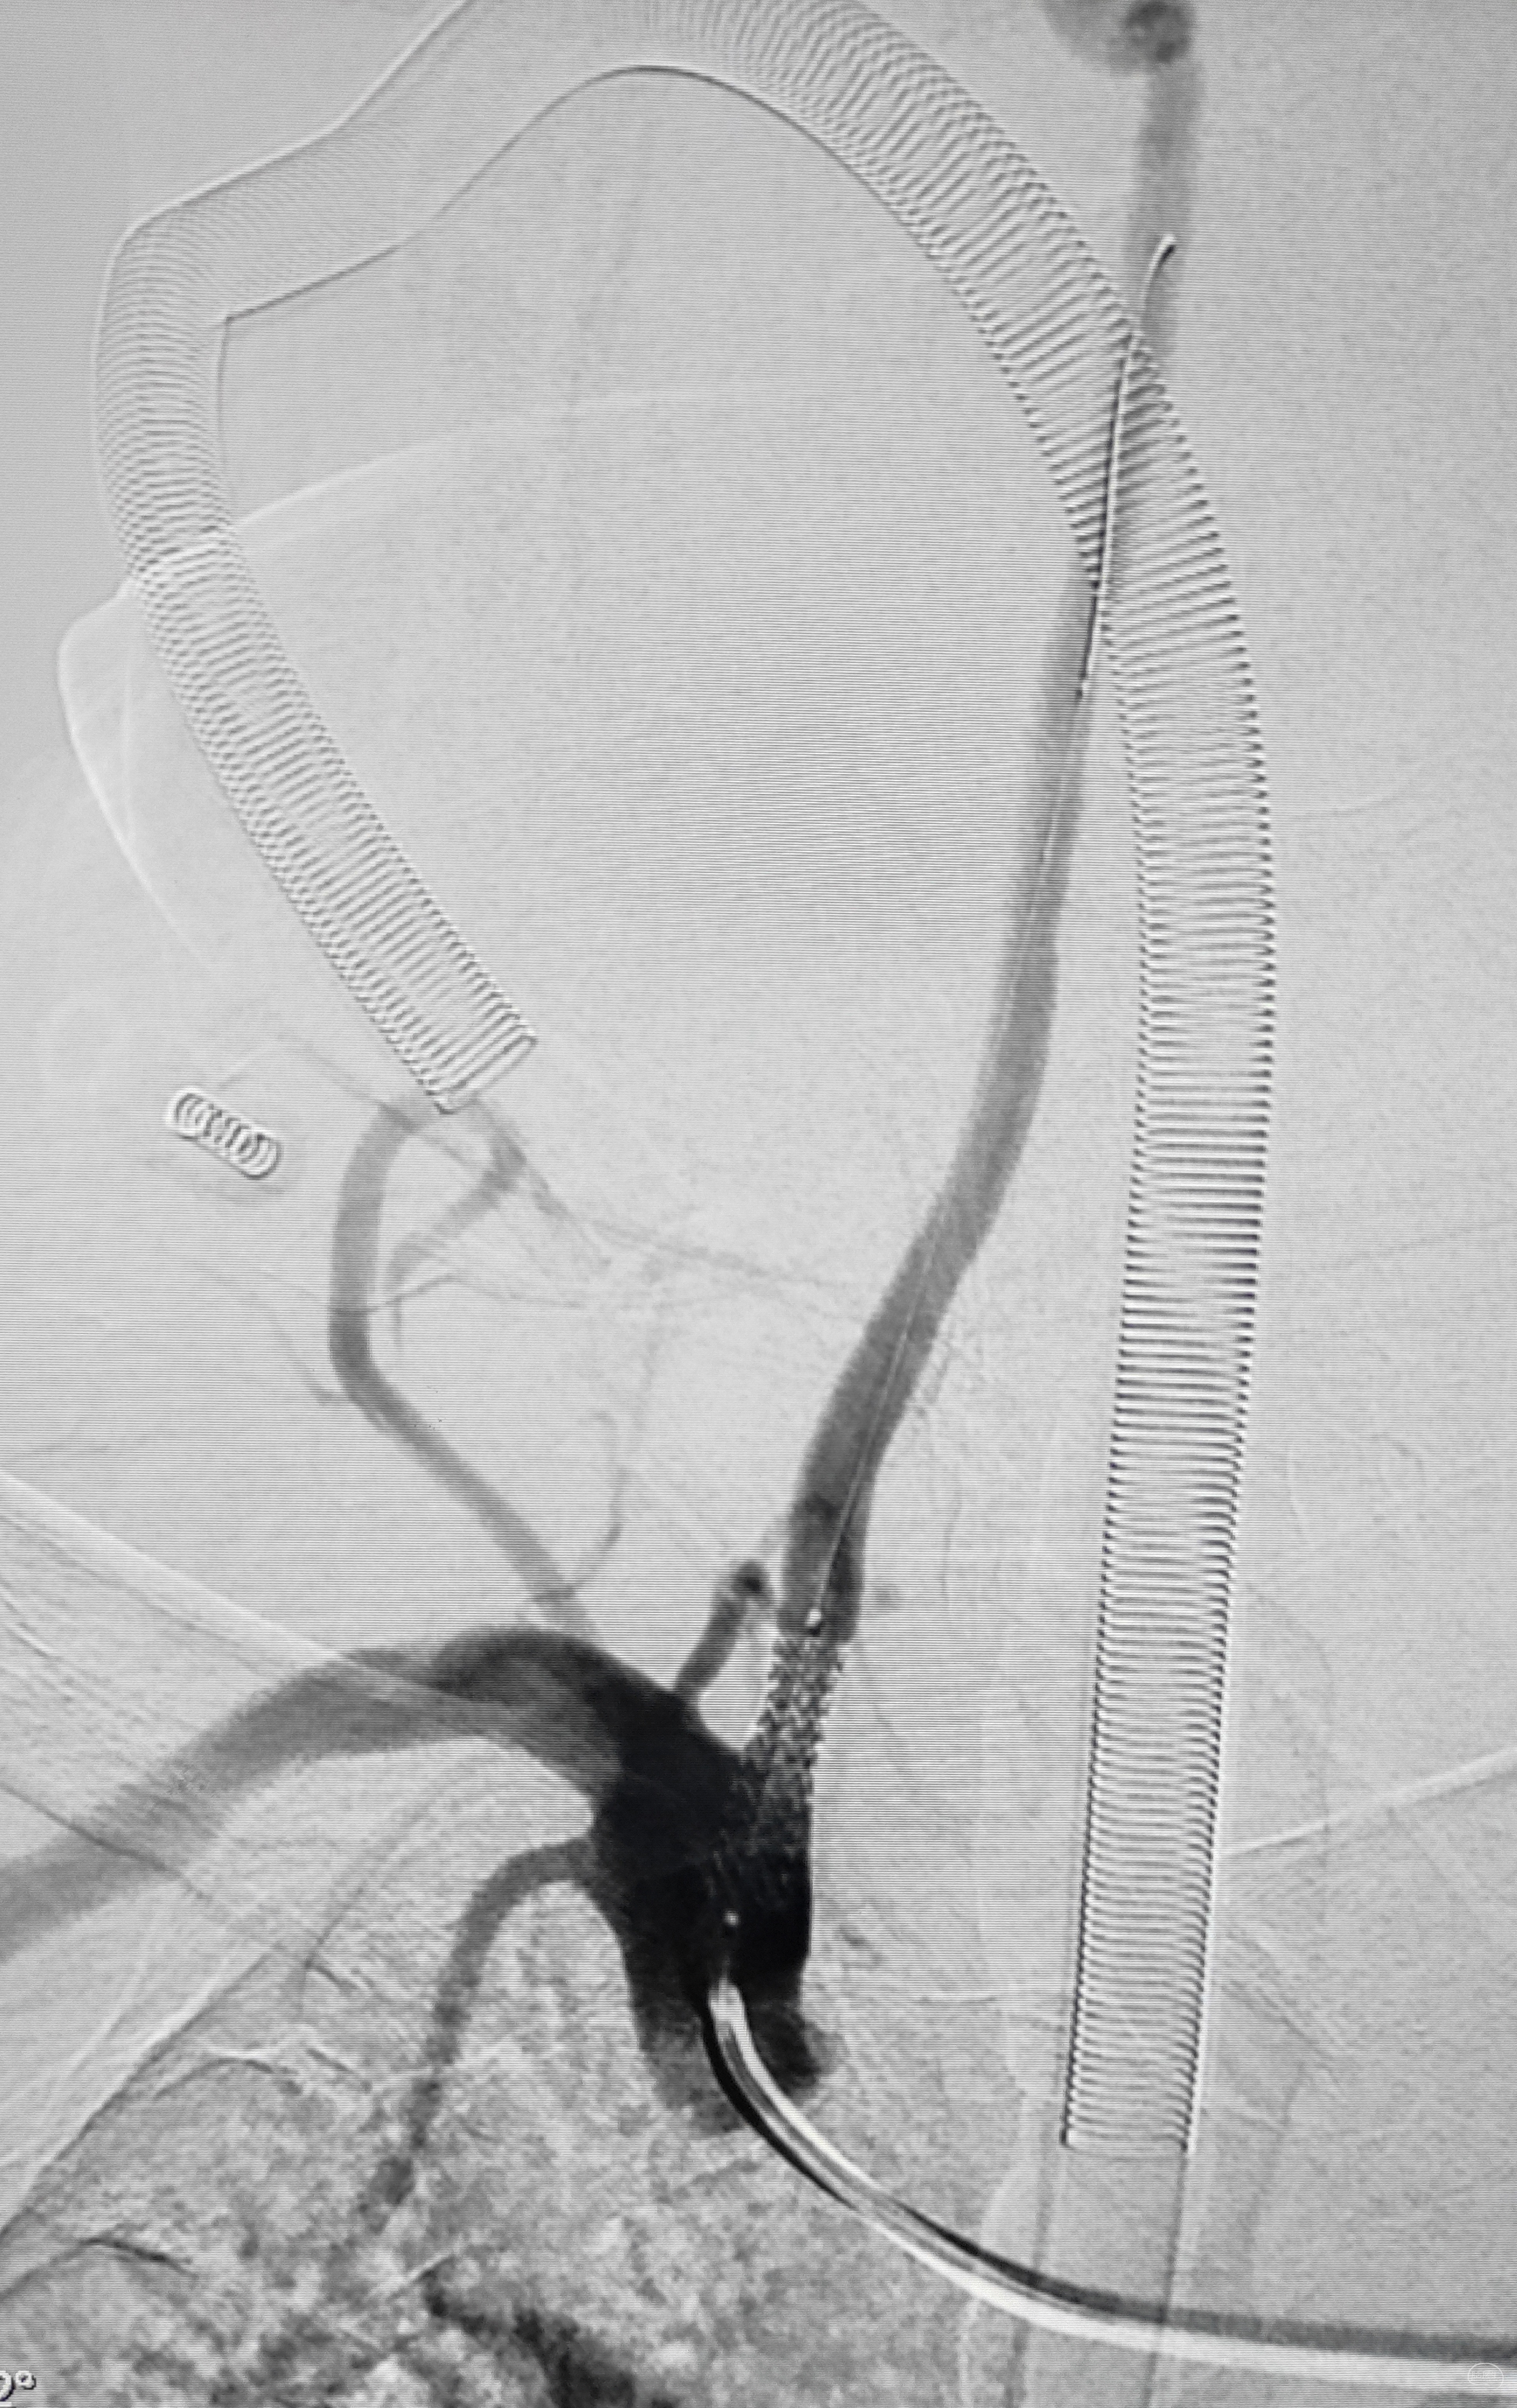

术后即刻造影,右侧椎动脉显影佳,并向左侧前循环代偿供血良好

第一步治疗结束,老人头晕症状消失,主诉解除,也许是尝到了治疗的甜头,积极要求尽快开通闭塞的左侧锁骨下动脉,劝他缓缓,三个月后再做,未果。女儿说出了心声:“我们看到了疗效,更佳信任。我希望自己返回上海工作前,把能做的都做好了,送父亲回山西老家,再回上海”,一时语塞,多孝顺啊,我们竟找不出拒绝的理由

支架导引导管内先通过,再回撤技术,顺利释放雅培9×29球扩支架